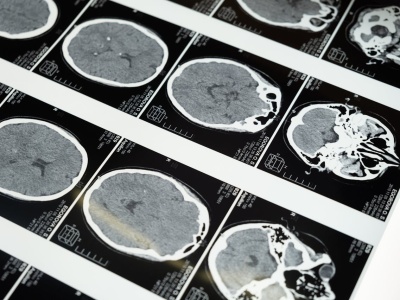

Lek przeciwnowotworowy abemacyklib daje nadzieję pacjentom z agresywnymi oponiakami. Artykuł Doustny lek na raka daje nadzieję na walkę z agresywnymi guzami mózgu pochodzi z serwisu Alert Medyczny.